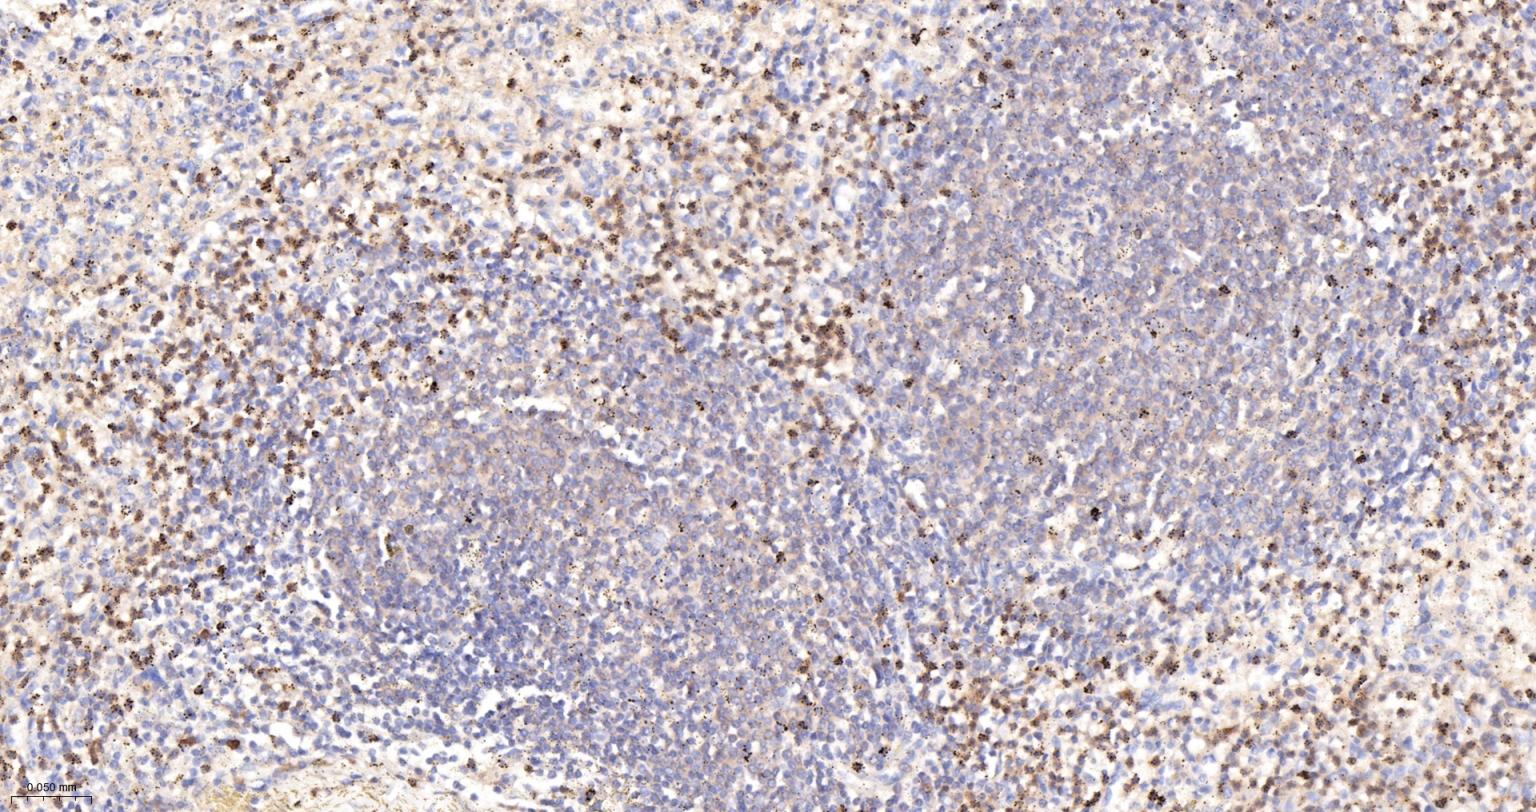

Paraformaldehyde-fixed, paraffin embedded Human Spleen; Antigen retrieval by boiling in sodium citrate buffer (pH6.0) for 15 min; Antibody incubation Glucose 6 Phosphate Dehydrogenase Monoclonal Antibody, Unconjugated(bsm-61479R) at 1:200 overnight at 4°C, followed by conjugation to the bs-0295G-HRP and DAB (C-0010) staining.